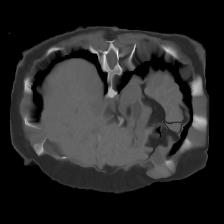

In clinical practice, well-aligned multi-modal images, such as Magnetic Resonance (MR) and Computed Tomography (CT), together can provide complementary information for image-guided therapies. Multi-modal image registration is essential for the accurate alignment of these multi-modal images. However, it remains a very challenging task due to complicated and unknown spatial correspondence between different modalities. In this paper, we propose a novel translation-based unsupervised deformable image registration approach to convert the multi-modal registration problem to a mono-modal one. Specifically, our approach incorporates a discriminator-free translation network to facilitate the training of the registration network and a patchwise contrastive loss to encourage the translation network to preserve object shapes. Furthermore, we propose to replace an adversarial loss, that is widely used in previous multi-modal image registration methods, with a pixel loss in order to integrate the output of translation into the target modality. This leads to an unsupervised method requiring no ground-truth deformation or pairs of aligned images for training. We evaluate four variants of our approach on the public Learn2Reg 2021 datasets \cite{hering2021learn2reg}. The experimental results demonstrate that the proposed architecture achieves state-of-the-art performance. Our code is available at https://github.com/heyblackC/DFMIR.

翻译:在临床实践中,如磁共振(MR)和光谱成像(CT)等非常相近的多模式图像可以一起为图像制导疗法提供补充信息。多模式图像登记对于这些多模式图像的准确匹配至关重要。然而,由于不同模式之间复杂的和未知的空间通信,这仍然是一项非常艰巨的任务。在本文中,我们提议采用新的、基于翻译的、不受监督的变形图像登记方法,将多模式登记问题转换成单一模式。具体地说,我们的方法包括一个无歧视翻译网络,以便利对登记网络的培训,以及一种有偏差的对比性损失,以鼓励翻译网络保存对象形状。此外,我们提议取代在以往多模式图像登记方法中广泛使用的一种对抗性损失,目的是将翻译的输出纳入目标模式。这导致一种不统一的方法,不需要地面图解或对齐图像来进行培训。我们评估了公共学习2MReg20的四种变式方法,我们在公共实验2Regmal-ress productions 2021我们提议的实验性结构中实现了2021号的运行结果。